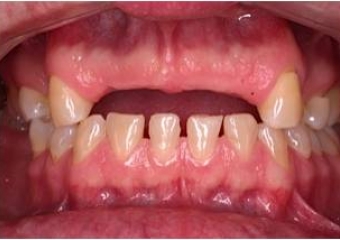

Sorriso final, do caso terminado em Novembro de 2012